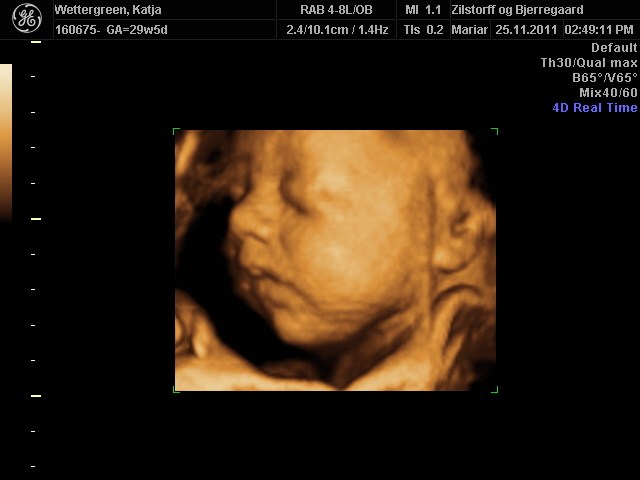

Her går det også godt, - er lige kommet hjem fra en fantastisk 3D scanning. Vores lille pige har det godt og er helt igennem fin! SÅ SØD! Hun har indhentet den manglende vægt og ligger nu lige over gennemsnittet med ca. 1500 g, så det er dejligt!

Jeg er blevet sygemeldt grundet lavt blodtryk, og jeg tror at dette også har haft en positiv indvirkning på hendes vægt. På mandag skal vi til vækstscanning på Hvidovre, - så må vi se om de er enige.